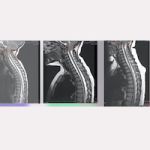

07/06/2013 Pre-SFT

30/07/2019 Post-SFT

Дата операции: 10/12/2013

Привет, я мама девочки, которую прооперировали в восемь лет по рассечению концевой нити в декабре 2013 года. Она стала четвертой пациенткой из Японии в Барселонском Институте Киари. Моя дочь страдает мальформацией Арнольда Киари I, идиопатическими сирингомиелией и сколиозом. С момента операции прошло уже шесть с половиной лет, и все идет очень хорошо. У нее была очень большая сирингомиелическая киста до поясничного отдела, но уже через шесть месяцев после операции она уменьшилась наполовину, а через 18 месяцев осталась только третья часть того, что было. Киста еще есть, но она понемногу уменьшается. Через два с половиной года появились первые изменения в положении миндалин мозжечка, а через четыре с половиной года произошло еще больше улучшений. Врач моей дочери в Японии был удивлен таким результатом рассечения концевой нити и сказал, что раз киста так сильно уменьшилась, то она не будет давать новых проблем. Однако, так как полностью остановить сколиоз уже было нельзя, Институт порекомендовал нам метод Шрот и через 4 месяца после операции моя дочь начала по нему заниматься. На четыре года мы смогли остановить развитие искривления, но когда дочка вступила в подростковый период, в декабре 2018 года, ее сколиоз ухудшился до 48 градусов, поэтому мы решили поменять центр реабилитации, и уже через месяц она улучшила результат до 33 градусов, и мы продолжаем занятия, чтобы снизить сколиоз.

07/06/2013 Pre-SFT

07/06/2013 Pre-SFT 30/07/2019 Post-SFT

30/07/2019 Post-SFT The Filum disease and the Neuro-Cranio-Vertebral Syndrome: definition, clinical picture and imaging features.